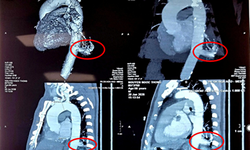

Nhận bệnh nhi đa chấn thương nghiêm trọng, bác sĩ đưa thẳng vào phòng mổ, nỗ lực cứu

Y tế - 16/05/2024 09:57SKĐS - Sáng 16/5, thông tin từ Bệnh viện Việt Đức cho biết các bác sĩ của Bệnh vừa báo động đỏ, đẩy thẳng bệnh nhi đa chấn thương vào phỏng mổ để vừa hồi sức vừa làm chẩn đoán và phẫu thuật, nỗ lực cứu bé gái.